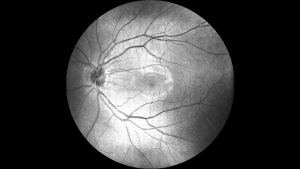

• Зображення сітківки в режимі реального часу під кутом 45° SLO

High quality real-time SLO + Eye tracking

Висока якість SLO в реальному часі + відстеження руху очей

Mocean® 3000 одночасно отримує ОКТ-зображення і зображення очного дна під кутом 47 градусів на основі скануючого лазерного офтальмоскопа (SLO), забезпечуючи огляд сітківки в режимі реального часу, що дозволяє легко локалізувати ділянку ураження ще до отримання зображення.